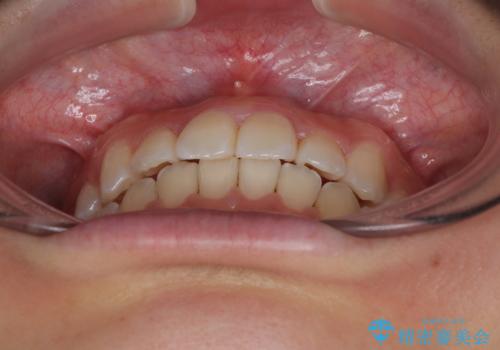

- 上顎前歯のクロスバイトを気にして来院された患者様です。

ワイヤー矯正でもマウスピース矯正でも対応可能でしたが、マウスピースによる自己管理に一切の自信がないとのことで、ワイヤー装置にて矯正治療を行うこととしました。

装置の外見を気にしていましたが、短期間で治療を終えることができるだろうと伝えると、安価であるメタルブラケットを選択されました。

想定通り、1年強で綺麗に仕上げることができました。